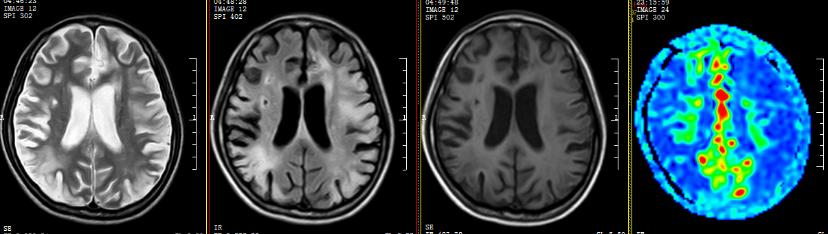

我院ASL序列提示:双侧额颞岛顶枕叶多发片状低灌注区,以额颞顶叶低灌注较明显;DSA提示:烟雾病,双侧颈内动脉末端闭塞,颅底可见烟雾样血管生成并向远端代偿,可见右侧颈外动脉系统对颈内系统部分代偿。

▲左侧脑血管重建术后3个月复查

仔细考虑之后,佳佳决定先接受左侧脑血管重建术(脑-硬脑膜-动脉-颞肌血管融合术)。术后回家休养了3个月后,佳佳遵医嘱到院复查。复查ASL序列提示右侧大脑半球、左侧额顶叶仍示多发片状低灌注区,左侧额颞岛叶灌注较前增高、明显代偿;DSA提示右侧颈外动脉向颅内无代偿,左侧颈外动脉向颅内代偿明显,颅内供血增加。

▲双侧脑血管重建术后一年复查

这次到医院复查,佳佳的精神态势非常好,让人很难把眼前这个开朗明媚的女孩与一年前那个病态十足的患者联想起来。复查影像提示:双侧脑血管重建术后,双侧颞浅动脉脑膜副动脉经软膜向颅内动脉吻合代偿。这下,佳佳一家总算是可以放心了。